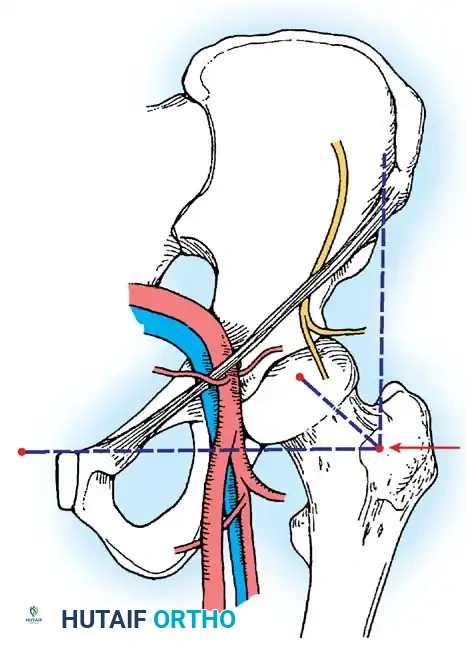

Arthroscopic Portal Anatomy and Safe Zones

Accurate portal placement is the cornerstone of safe hip arthroscopy. The hip is surrounded by major neurovascular structures, making adherence to anatomical landmarks non-negotiable.

2. The Anterior Portal

Used primarily as a working portal for the anterior labrum and cam decompression.

- Location: Placed at the intersection of a vertical line drawn inferiorly from the anterior superior iliac spine (ASIS) and a transverse horizontal line drawn from the superior margin of the greater trochanter. Extended medially, this line sits just superior to the symphysis pubis.

- Anatomy Traversed: Penetrates the sartorius and rectus femoris muscles before entering the anterior capsule.

- Structures at Risk: The Lateral Femoral Cutaneous Nerve (LFCN) and the ascending branch of the lateral femoral circumflex artery.

Surgical Warning: To avoid transecting the LFCN, use a superficial skin incision only. Bluntly dissect and spread the subcutaneous tissues with a hemostat down to the capsule before passing the cannula. The blunt trocar will safely push the nerve aside.

3. The Posterolateral Portal

Used for viewing the posterior labrum and removing posterior loose bodies.

- Location: Just superior to the margin of the greater trochanter at its posterior border.

- Trajectory: Directed slightly cephalad and anteriorly, converging toward the anterolateral portal.

- Anatomy Traversed: Traverses the gluteus medius and minimus muscles.

- Structures at Risk: The sciatic nerve. It is imperative to have the hip in neutral rotation while establishing this portal to maximize the distance between the portal tract and the sciatic nerve.